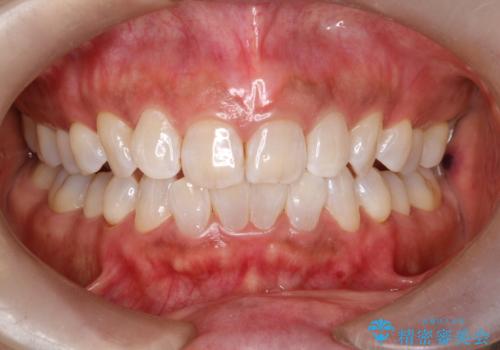

オフィスホワイトニング スペシャルコース

1回来院で白くしていくホワイトニングではなく、何回か受けて頂き、徐々に白くしていくコースとなります。知覚過敏が心配な方やホームホワイトニングをしながらの方にもおすすめです。

銀座では1番人気コースです。